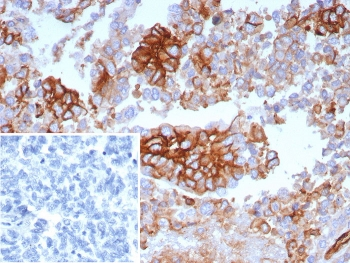

IHC staining of FFPE human ovarian carcinoma tissue with SLC2A1 antibody (clone GLUT1/7308). Inset: PBS used in place of primary Ab (secondary Ab negative control). HIER: boil tissue sections in pH9 10 mM Tris with 1 mM EDTA for 20 min and allow to cool before testing.